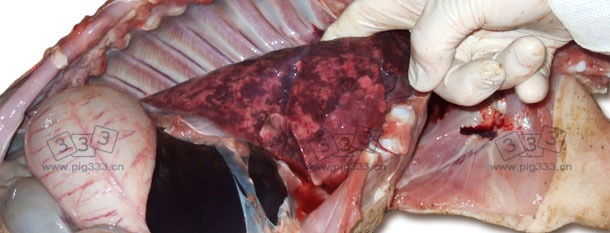

图片1.间质性肺炎多表现出的肺部增大,斑片状肺,肺部呈橡胶状

母猪出现繁殖障碍后一个月,6-8周龄的断奶仔猪又出现了对抗生素无反应的急性呼吸紊乱及腹泻症状。在这些症状被发现1个月后,该猪群的死亡率从1.8%上升到了4.5%。同期,健康状况低下的断奶仔猪的比例从4%上升至7.9%(图1b)。对4头8周龄左右的病死猪进行尸检发现:淋巴结及肝脏肿大、肾脏肿大且颜色苍白,并伴有大面积的皮质淤血。对淋巴结的显微镜分析显示出在被检猪中存在不同程度的淋巴细胞减少和组织细胞渗透。利用带PCV2DNA探针的原位混合法(ISH)发现病灶处出现大量的PCV2 DNA。组织病理学说和临床症状均满足PMWS病例的定义标准。